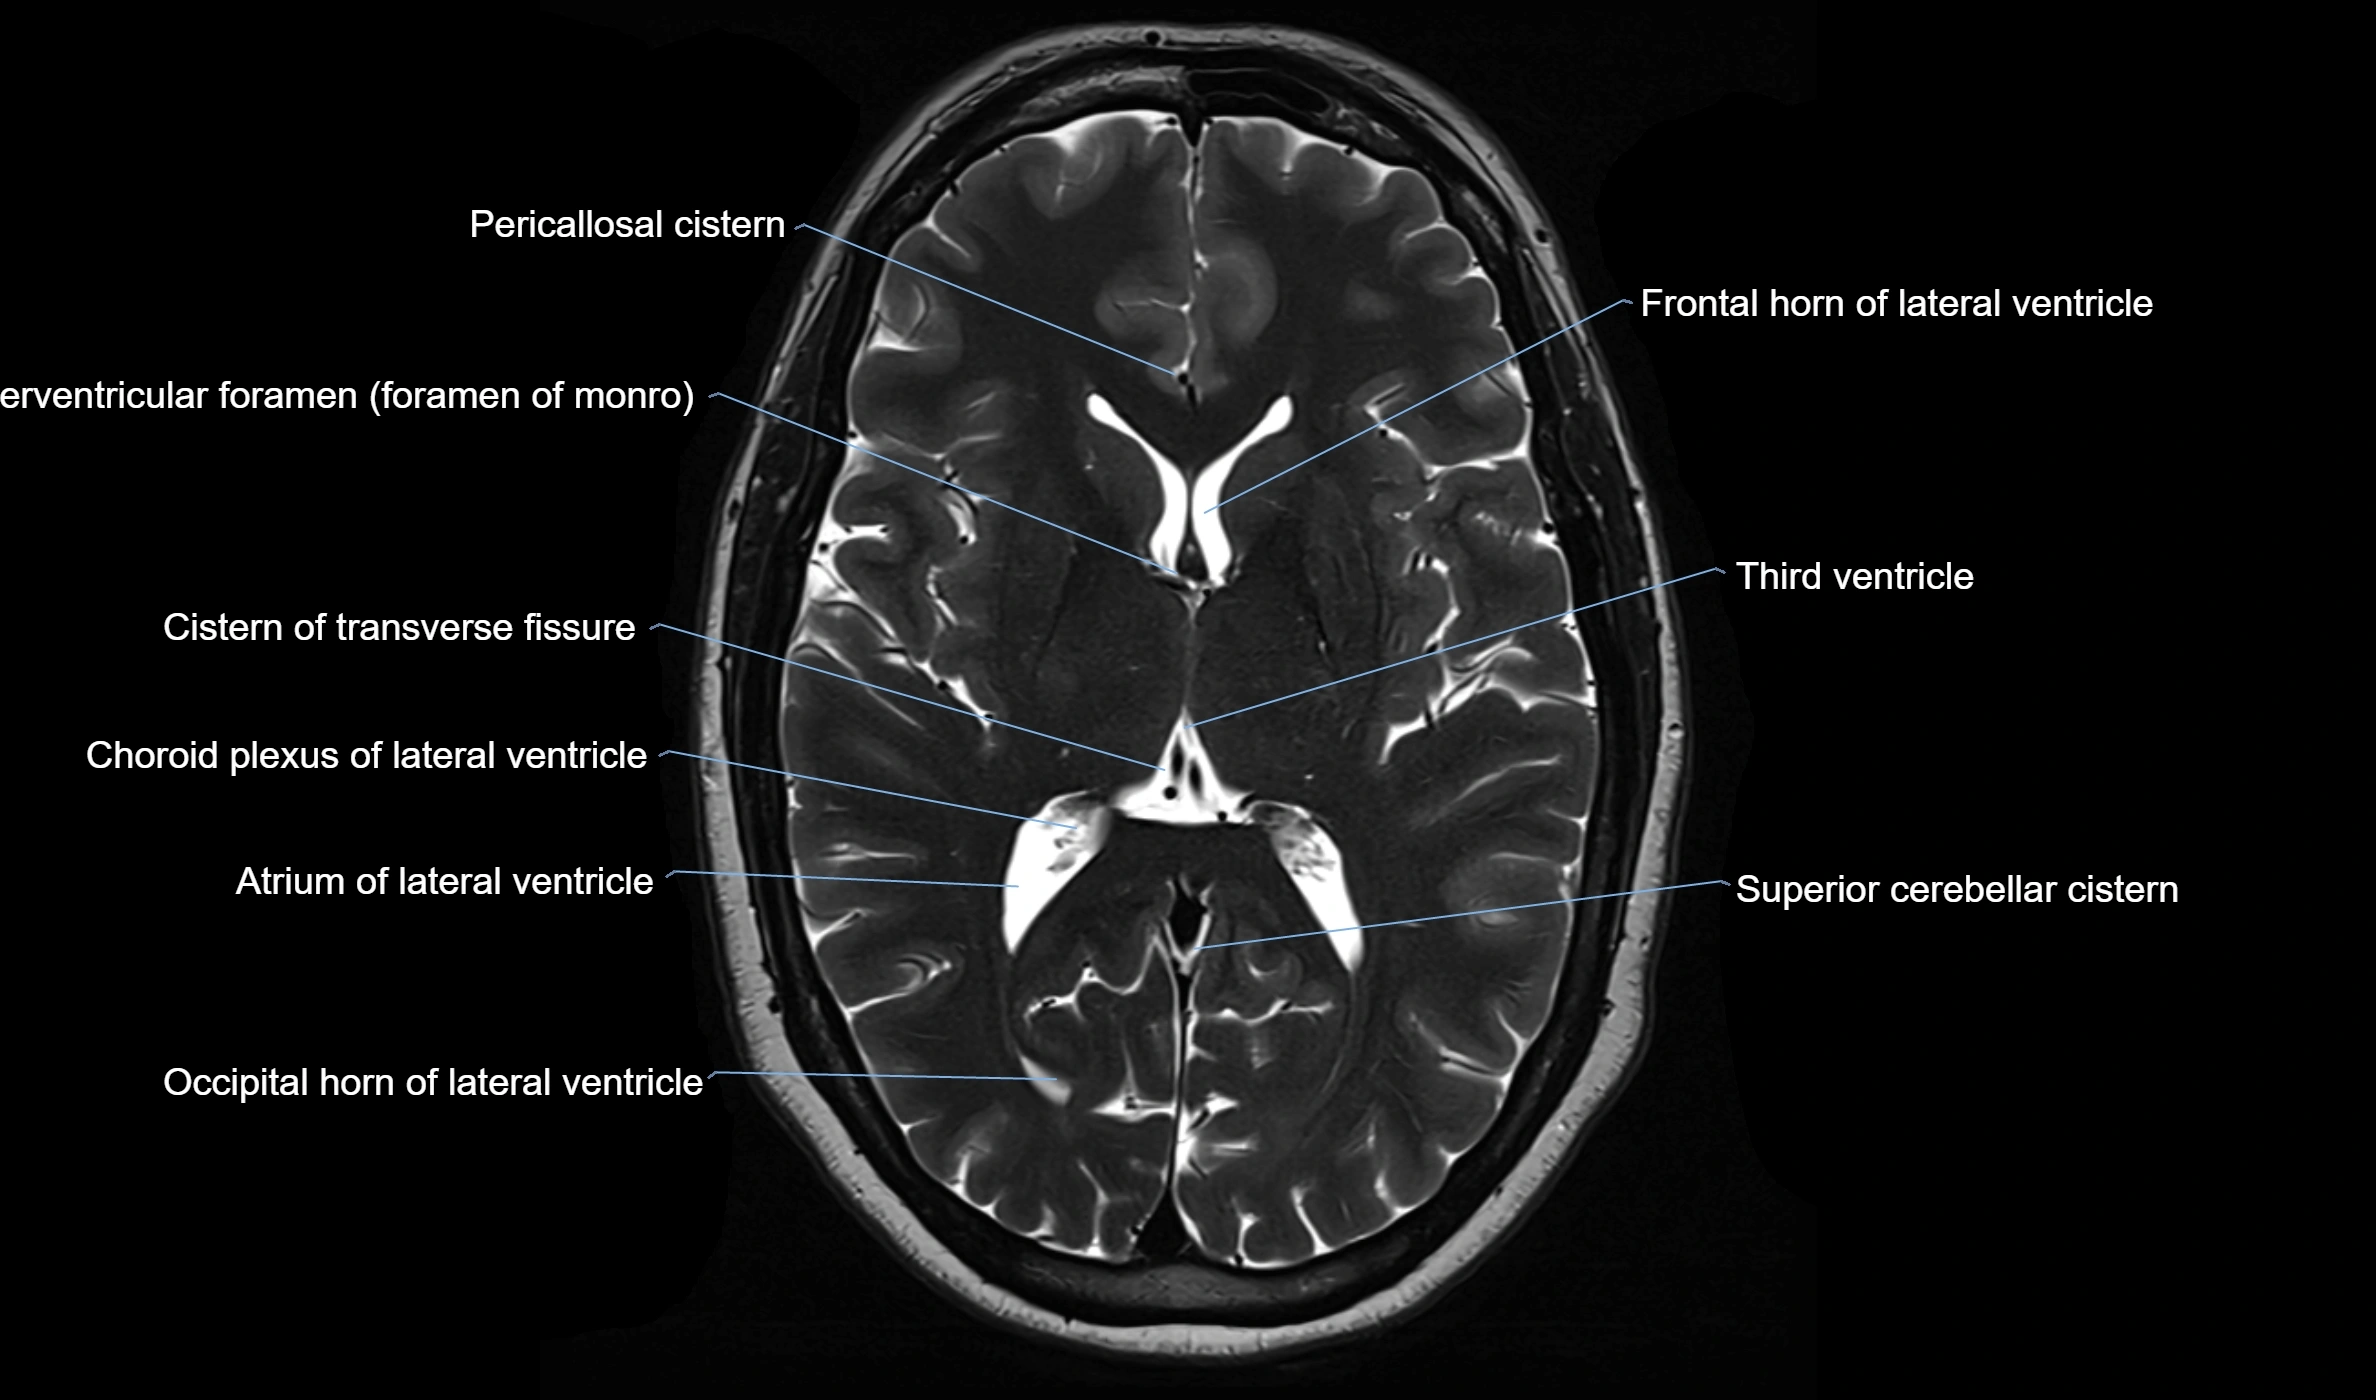

MRI images

image